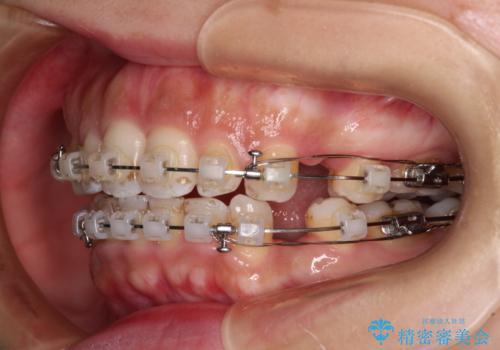

唇が閉じにくい ワイヤー装置での抜歯矯正

- 矯正装置

- クリアブラケット

- 唇が閉じにくく、上の前歯が下唇に当たって気になるとのことで来院された患者様です。

レントゲン写真での分析結果からは、抜歯矯正をするかどうか悩む境界線上でしたが、主訴が口元の突出感であったため、上下左右の第一小臼歯4本を抜歯して矯正治療を行うこととしました。

上下ともに前歯が少し舌側に傾斜したような仕上がりとなりましたが、口が閉じやすくなったとのことで、患者様には大変満足していただけました。